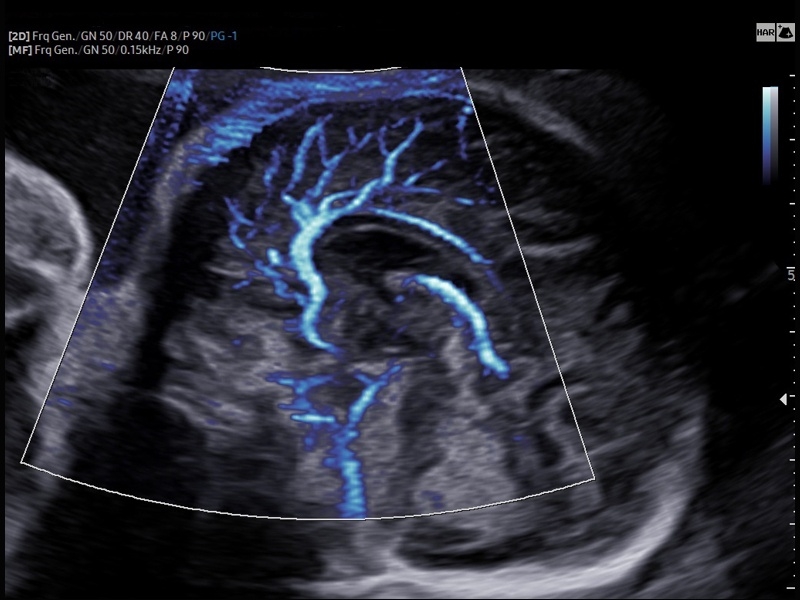

• Модуль MV-Flow – программа (режим), позволяющая визуализировать кровоток в микроциркуляторном русле с высоким разрешением без использования контраста.

• Модуль LumiFlow – программа отображения кровотока с объемной графикой для лучшего понимания архитектоники сосудистого русла.